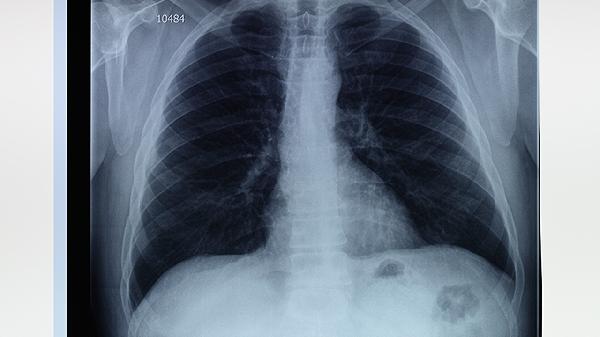

2、肺大泡的症状与诊断

大多数肺大泡患者无症状,通常在体检或影像学检查中被偶然发现。若肺大泡较大或合并感染,可能出现呼吸困难、胸痛或咳嗽等症状。诊断主要依赖胸部CT扫描,CT可以清晰显示肺大泡的大小、位置和数量,帮助医生评估病情。对于无症状的肺大泡,通常无需特殊治疗,但需定期随访观察。